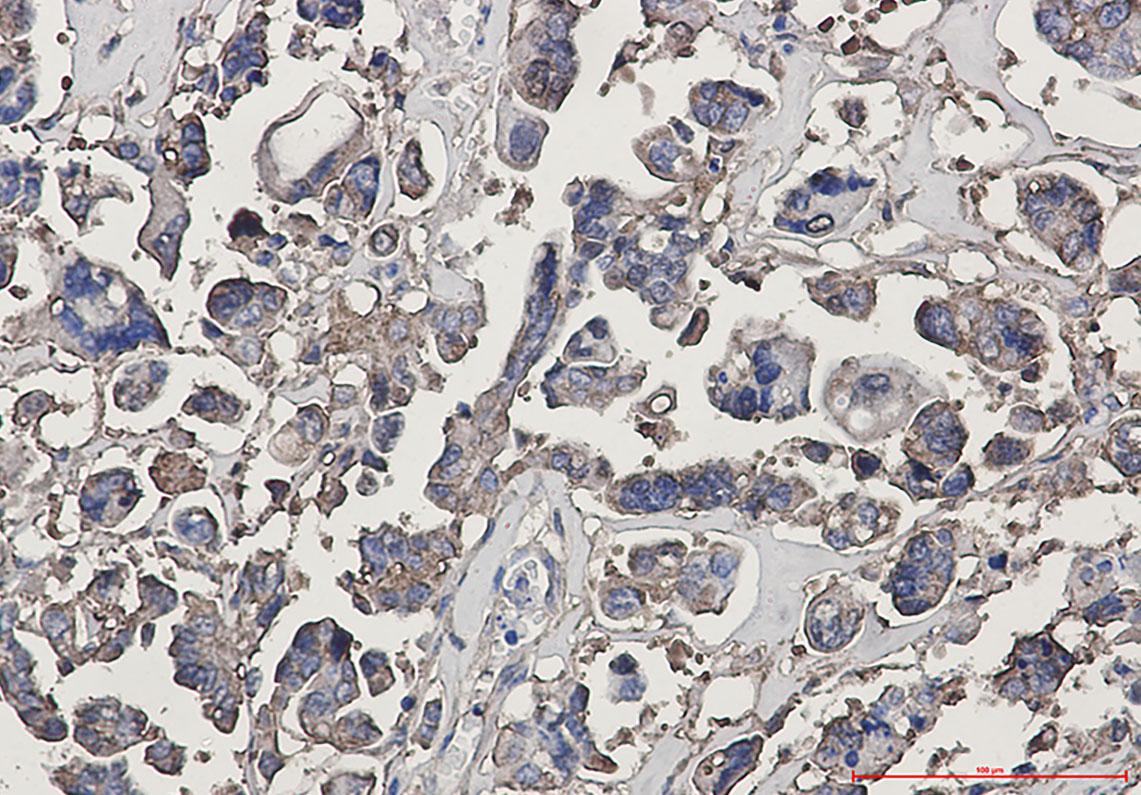

- Immunohistochemistry analysis of paraffin-embedded Human Cholangiocarcinoma using beta III Tubulin antibody. High-pressure and temperature Sodium Citrate pH 6.0 was used for antigen retrieval.